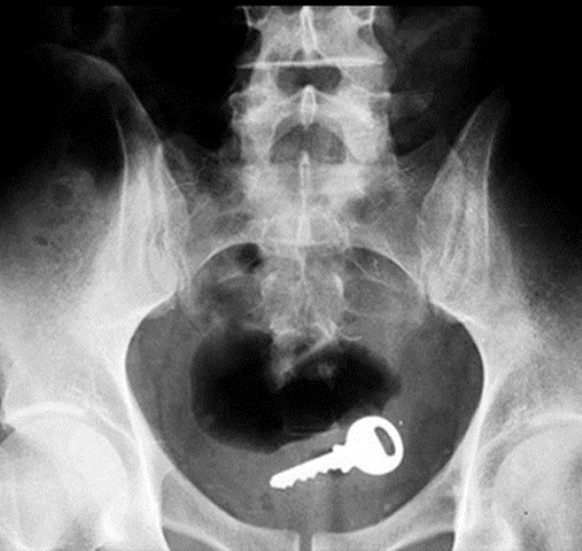

Ich kann nichts sehen, mach mal Licht hier

Schlüssel verloren? Such mal hinten.

Zu dunkel? Nimm eine Taschenlampe!